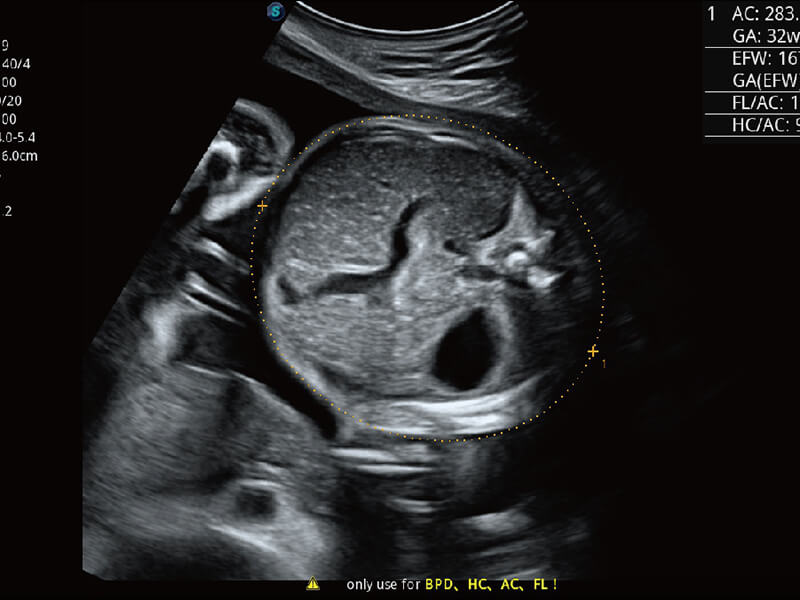

彩色多普勒超声诊断系统

S60探头工艺,从前端信号处理每一个环节采集无损声学数据,真实还原组织原貌,再现解剖细节。

超宽频带技术,为容积成像带来优质的二维图像基础,为您呈现丰富的结构细节,栩栩如生地展示宝宝的宫内形态以及各种组织的立体结构。